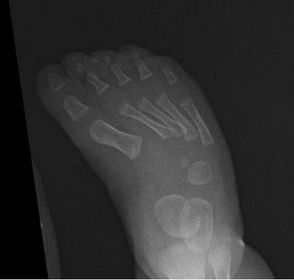

Describe the alignment of metatarsal 2 | There is no angulation nor displacement of the distal segment relative to the proximal segment. |

Describe the alignment of metatarsal 3 | The distal segment is displaced laterally (50% apposition) and angulated medially. |

Describe the alignment of metatarsal 4 | The distal segment is displaced laterally (75% apposition) but there is no apparent angulation. |

Describe the tubulation of the metatarsals | Metatarsals are overtubulated - decreased girth. |